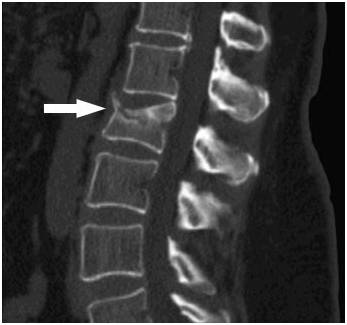

Грыжа позвоночная поясничного отдела ущемляет нерв, в результате чего он воспаляется

- Грыжа межпозвоночного диска – выбухание его пульпозного ядра в спинномозговой канал вместе с разрывом фиброзного кольца.

Разрушение тела позвонка в поясничном отделе на снимке КТ